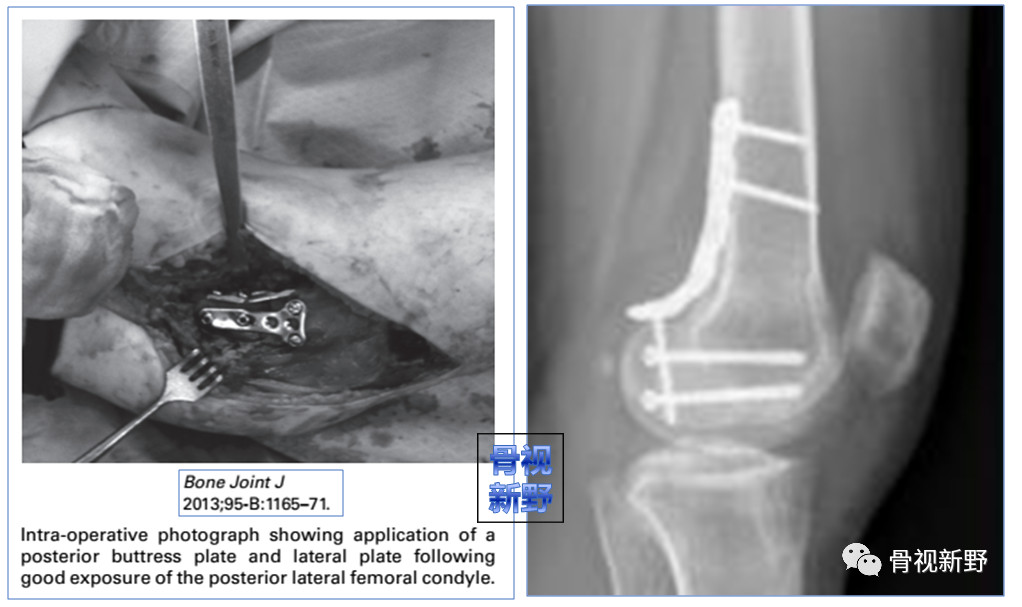

Buttress理念:由于Hoffa骨折垂直剪力较大,单纯拉力钉固定易致骨折移位、畸形愈合或不愈合。

因此,使用防滑、支撑的Buttress钢板以对抗垂直剪力有一定的必要性。